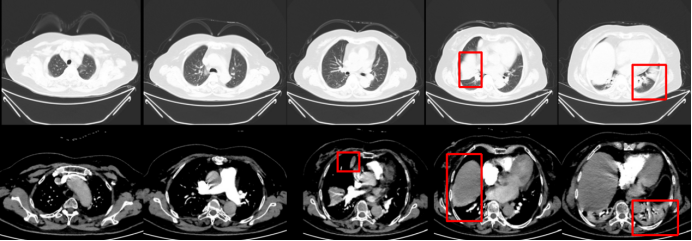

7月14日,动态胸片示双侧膈肌移动度正常。平静呼吸时,右侧膈肌移动度为12.0 mm,左侧为16.0 mm(图8);尽力呼吸时,右侧膈肌移动度为48.0 mm,左侧为50.0 mm(图9)

8月14日复查胸部CT:病变较前明显吸收改善(图10)

图片

8  平静呼吸时动态胸片(2025-07-14)

9  尽力呼吸时动态胸片(2025-07-14)

10  胸部CT对比图片

注:膈肌抬高、双下肺不张逐步好转。